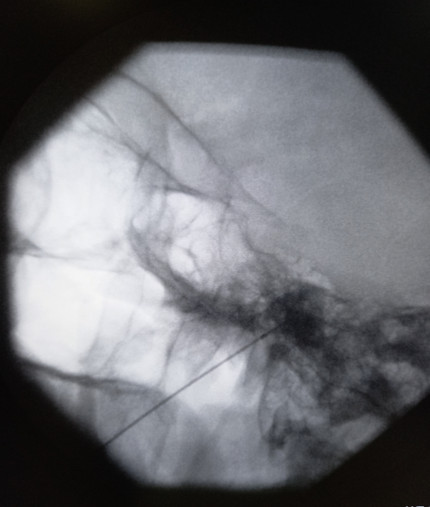

Hydrodilatation is a simple, minimally invasive treatment for frozen shoulder. It’s usually done in a clinic with a needle, although in more complex cases, it may be done in a special treatment room with X-ray guidance. The goal is to inject fluid into the shoulder joint to stretch the thickened joint capsule, help reduce inflammation and improve movement, and it can be done at any stage of the condition. This procedure is very effective. Most people see a big improvement in their shoulder's range of motion after just one injection. It not only helps with movement but also relieves pain, which is important because pain can make it harder to stretch the joint and improve mobility. Recovery is usually quick, and most patients can return to normal activities the same day. It's also recommended to do stretching exercises to help with recovery. Hydrodilatation is generally safe when done by experienced specialists, but it’s important to talk to your doctor about the benefits, risks, and other options before deciding if it’s right for you.